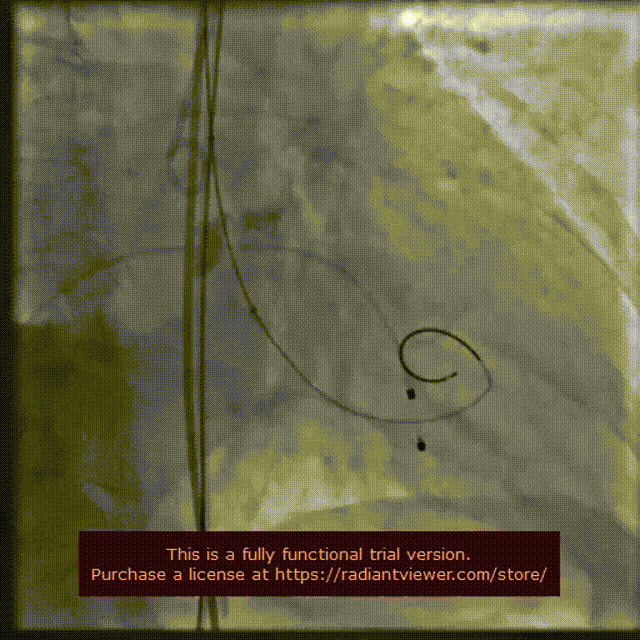

18 mm球囊后扩

瓣膜完整形态

术者团队观察到瓣膜形态未能完全伸展,为取得更好治疗效果,后续予以后扩处理。采用18 mm球囊进行后扩后扩,行主动脉造影提示瓣膜置入位置良好、形态完整。